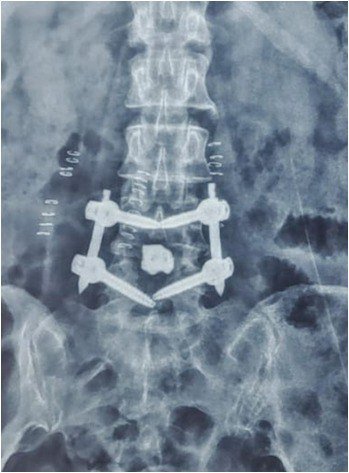

- Bone graft and cage are placed between vertebrae

- Pedicle screws and rods stabilize the spine

- Fusion progresses over several months